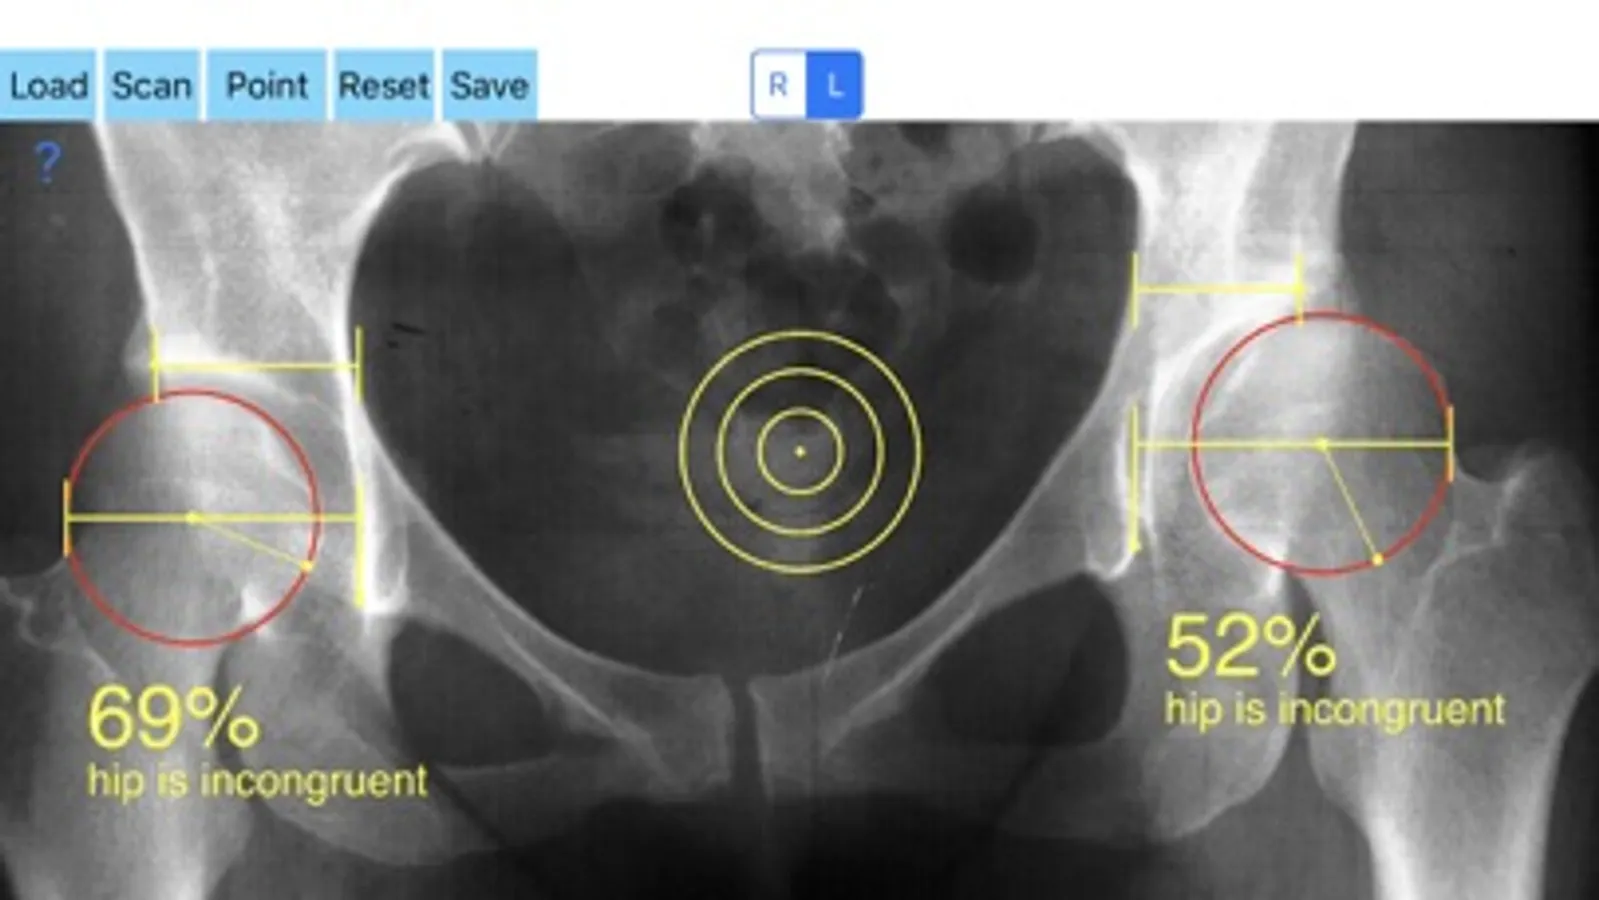

Treatment of incongruity is paramount importance because you have to address it early and the treatment of choice are usually corrective hip osteotomies. In order-from one hand to avert the natural course to the progression of secondary osteoarthritis (OA) and from another hand to avoid- in developing skeleton - to deteriorate more the hip dysplasia the congruity must be objectively and thoroughly evaluated especially at follow up of these procedures in both congruent and incongruent hips. Congruity between the femoral head and acetabulum is determined by the percentage of femoral head covered by the bony acetabulum. The congruity index (CI) is calculated (A/B- ratio converted to a percentage) by diving the (A) distance by the distance (B), where distance (A) is the distance between the teardrop to the lateral acetabular margin and (B) is the distance from the teardrop again to the lateral femoral head edge.

-Offers a very convenient way to determine the most accurate possibly way an objective value of congruity. By clicking three point at the x-ray picture on your iPhone screen and inserting the side the App calculates the congruity index (CI) which is the percentage of femoral head covered by the bony acetabulum. Congruity between the femoral head and acetabulum is expressed in percentage. Values of Coverage less than 75% is considered pathologic in another words the hip is incongruent